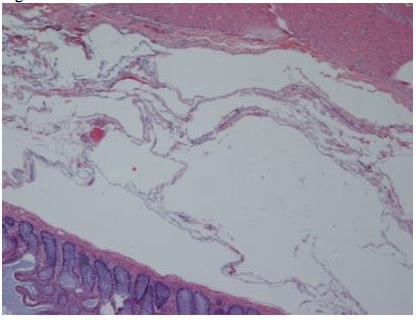

A 28-year-old woman with a history of acute myelogenous leukemia (AML), aggressively treated with 3 bone marrow transplants and multiple regimens of chemotherapy targeting AML, presented to the emergency room with abdominal pain and fever. Computed tomography (CT) of the abdomen and pelvis revealed pneumatosis of the transverse colon and a small amount of free air adjacent to the lesser sac (Figure 1).

Figure 1

Computed tomography (CT) of the abdomen and pelvis revealed pneumatosis of the transverse colon and a small amount of free air adjacent to the lesser sac.